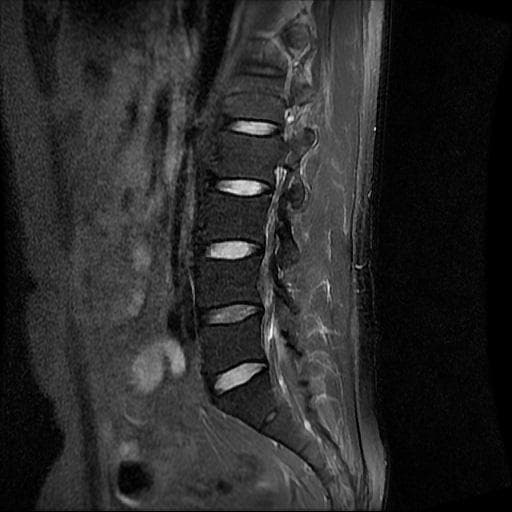

허리 MRI 디스크 상태 분석 부탁드립니다

검진 차 MRI찍었는데 분석 부탁드립니다.

건협에서는 관리해야 된다는데 디스크 협착이나 팽윤 등이 있는 상태인지 궁금합니다.

우선 현재로썬 사진만으론 판단을 하기에 제한이 되지만 사진상 디스크 상태는 심해보이지 않습니다.

요추부위의 하부 에서 약간의 팽윤이나 돌출로 의심해볼수 있는 정도이지만, 정확한 상태는 관련 전문의에게 진료시 문의를 하시는 것을 추천드립니다.